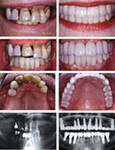

Имплантаты костные-Импланта?ты (также ошибочно импла?нты, имплантанты ((англ. implant - вживлённая (пересаженная) ткань) — класс изделий медицинского...

активный контакт с костной тканью по всей длине имплантата Сжатие кости в горизонтальном направлении с помощью резьбовых соединений квадратного сечени...